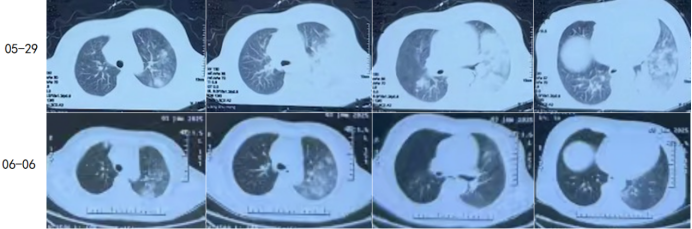

在此基础上,医疗团队携带氧气袋为患者复查胸部CT结果显示,患者肺内渗出性阴影较前明显吸收(图3),进一步印证了治疗方案的有效性。

3  治疗前后肺CT比较